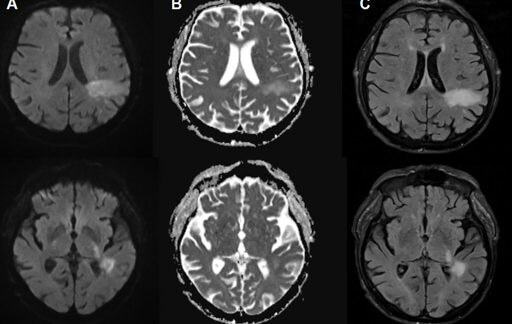

For the vast majority of people, that is all their JC virus infection will be—silent. But for an unlucky few, the JC virus will seemingly awaken, rearrange its genetic material, and morph into a brain-demolishing nightmare that causes a disease called progressive multifocal leukoencephalopathy or PML.